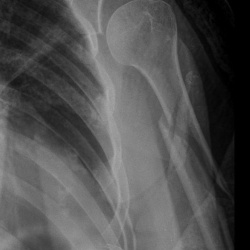

Мужчина 40 лет. Диагностическая  флюорография. Пришел на контроль, был поставлен диагноз 01.11.25 пневмония с\д, справа, в другой клинике. Смущает тень, которая видна только на задней проекции,...